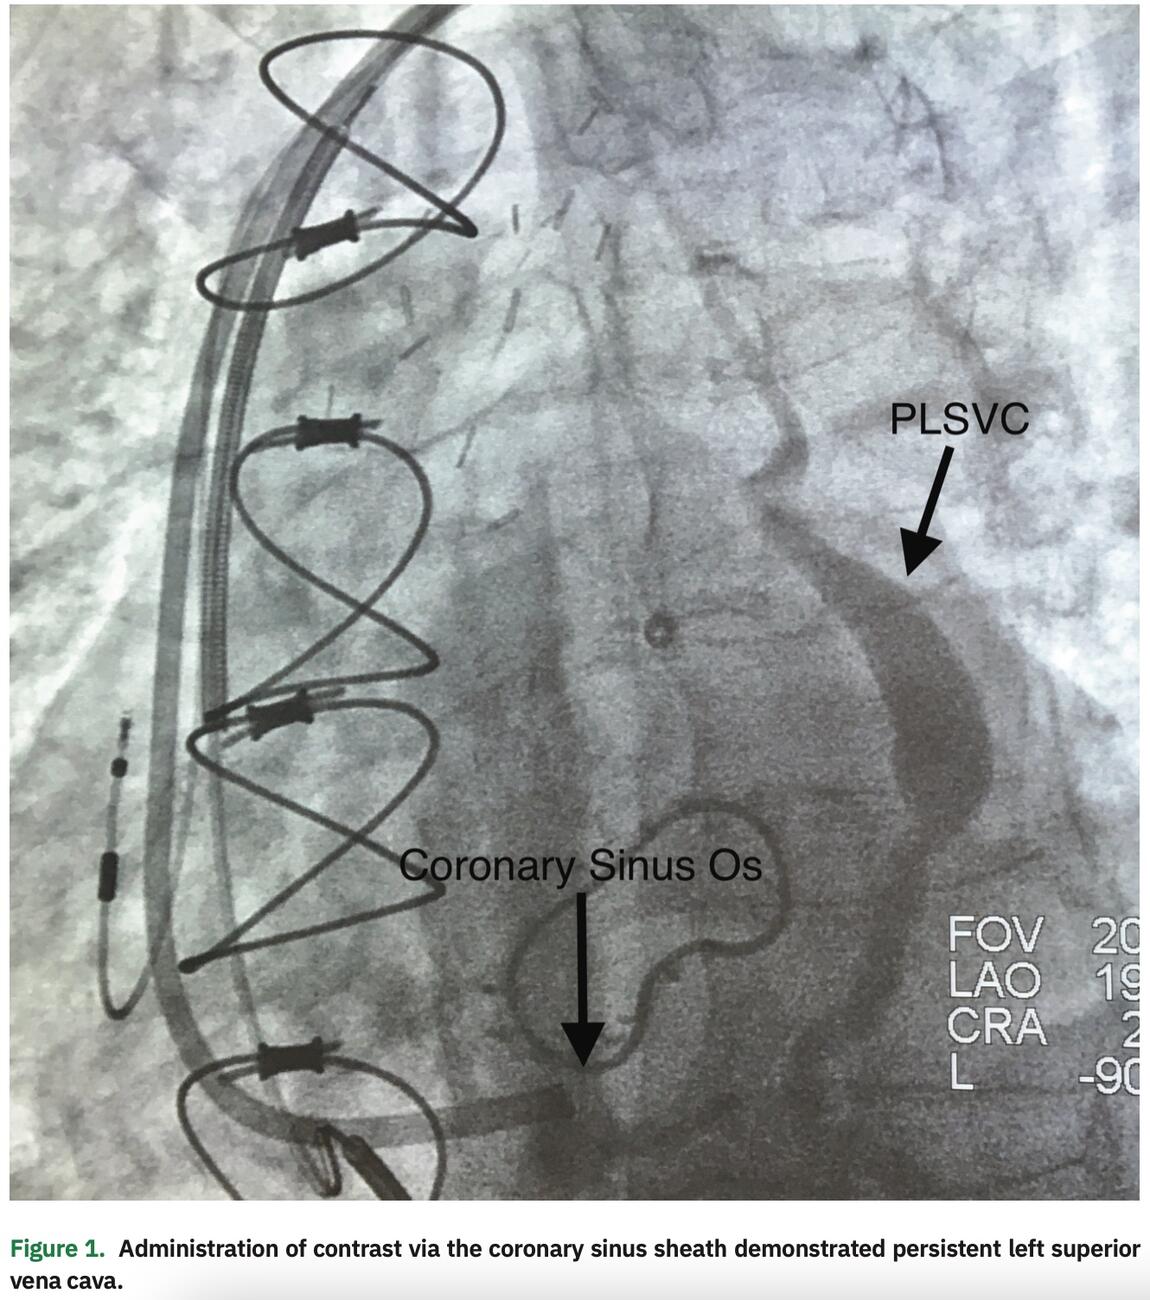

Subsequently, we attempted to selectively engage the CS ostium; however, an obstruction was encountered. An inner catheter was then used to partially engage the coronary sinus ostium, although the CS sheath could not be advanced. Angiography, via the CS sheath, revealed a subtotal occlusion and retrograde flow through what appeared to be a remnant vein of Marshall, but with a connection to the left innominate vein, consistent with a small PLSVC (Figure 2). Due to the CS ostial stenosis, the vein of Marshall or PLSVC provided venous return of the heart via its connection to the left innominate vein.

Given the subtotal occlusion, it was decided to abandon any further attempts of placement of the CS lead through the ostium. Rather, we proceeded with placement of the CS lead using the PLSVC. The previous venogram (Figure 1) demonstrated a medium to large caliber lateral vein without significant branching, which could be targeted with a quadripolar LV pacing lead. The inner catheter was utilized to subselect the PLSVC and deliver the lead into the lateral vein, which resulted in a stable lead position with adequate pacing and sensing characteristics. The greatest stability was achieved with the distal lead location within this vein. This site also provided an excellent pacing complex without diaphragmatic stimulation (Figure 4).